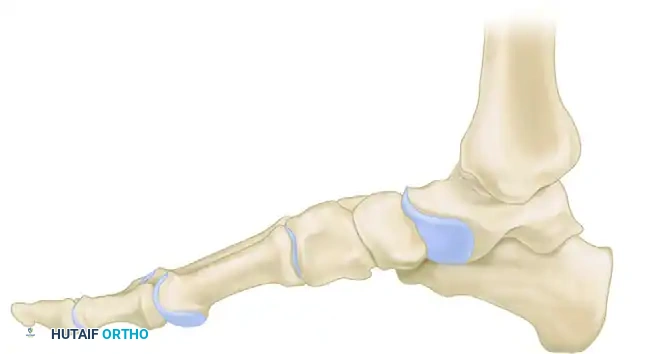

لفهم كيفية تأثير اعتلال مفصل شاركو على القدم، من الضروري إلقاء نظرة مبسطة على التشريح المعقد لهذه المنطقة. تتكون القدم من شبكة متداخلة من العظام، والمفاصل، والأربطة التي تعمل معاً لتوزيع وزن الجسم وتوفير الحركة المتوازنة.

تنقسم القدم تشريحياً إلى ثلاثة أجزاء رئيسية:

* القسم الخلفي: يشمل عظم العقب وعظم الكاحل، وهو المسؤول عن تحمل الجزء الأكبر من وزن الجسم عند الوقوف.

* القسم الأوسط: يتكون من مجموعة من العظام الصغيرة التي تشكل قوس القدم، وترتبط معاً بمفاصل دقيقة مثل مفاصل ليزفرانك.

* القسم الأمامي: يضم عظام المشط والسلاميات التي تشكل أصابع القدم.

في حالة قدم شاركو، غالباً ما يكون القسم الأوسط من القدم هو الأكثر عرضة للانهيار، مما يؤدي إلى تسطح قوس القدم وبروز العظام نحو الأسفل، وهو ما يعرف بتشوه الكرسي الهزاز. هذا التغير في البنية التشريحية يغير من نقاط ارتكاز الوزن الطبيعية، مما يضع ضغطاً هائلاً على مناطق غير مهيأة لذلك، ويؤدي في النهاية إلى ظهور التقرحات الجلدية.